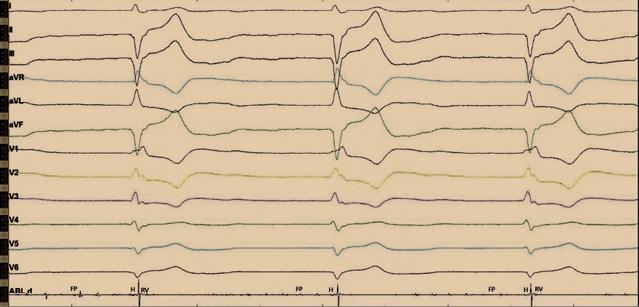

Рис. 2. Интраоперационное изображение с электрофизиологического монитора во время отключения электрокардиостимулятора. Отмечается нарушение внутрижелудочкового проведения по типу блокады правой ножки пучка Гиса и блокады передней ветви левой ножки пучка Гиса. Регистрируются эндограммы c аблационного катетера: фибрилляции предсердий (FP), проводящей системы (H) и высокоамплитудные желудочковые эндограммы (RV). На данном рисунке эндограммы H и FP трудно различимы между собой, однако стимуляция с картирующего электрода данной области позволяла получить стимуляционный комплекс, идентичный с нативным. Более выраженную эндограмму пучка Гиса зафиксировать не удалось. Предположительно, это связано с ранее проведенной аблацией атриовентрикулярного соединения

Рис. 4. Электрокардиограмма после операции. Отражена постоянная желудочковая стимуляция после имплантации гисиального электрода. Стимуляционный комплекс не расширен, соответствует нативному. Определяются стимуляционный спайк, изолиния и сокращение желудочков. Имеется также второй страхующий стимул, после которого нет ответа, по типу псевдосливного комплекса. Изолиния отражает замедление проведения по специализированным клеткам проводящей системы, с последующим сокращением по системе Гиса – Пуркинье. Длительность QRS составляет 110 мс

При эхокардиографии после операции незначительно увеличилась фракция выброса (53%). Сократительная способность миокарда левого желудочка сохранена. Перикардиального выпота нет. При программировании электрокардиостимулятора на следующие сутки нарушений функции детекции и стимуляции не выявлено (рис. 4). ЭКС работал в режиме DDD(R) с базовой частотой 60 ударов в минуту. Импеданс желудочкового электрода составлял 551 Ом, гисиального электрода – 464 Ом. Чувствительность желудочкового электрода была 8,5 мВ, гисиального электрода – 0,9 мВ. Порог стимуляции: хронический по желудочковому каналу – 0,7 В, гисиального электрода – 5,5 В при длительности импульса 1,5 мс. Амплитуда стимуляции была запрограммирована на 6,5 В при длительности импульса 1,5 мс, срок службы ЭКС – менее 5 лет. Учитывая малый срок службы ЭКС Medtronic Adapta и высокие параметры стимуляции, пациенту рекомендовано повторное программирование через 1 месяц.

Стимуляция проводящей системы сердца позволяет реализовать физиологическую стимуляцию у пациентов с нарушением предсердно-желудочкового проведения, что и было показано нами на данном клиническом примере. Выполненное оперативное вмешательство позволило снизить длительность комплекса QRS со 180 до 110 мс. Несмотря на блокаду ножек пучка Гиса, стимулированный комплекс имел длительность нативного. Высокий порог гисиального электрода обосновывает применение второго желудочкового электрода с целью страхующей стимуляции. На наш взгляд, использование страхующей стимуляции не только оправдано в связи с возможным ростом порога стимуляции в раннем и отдаленном послеоперационном периодах, но и служит гарантией при дислокации электрода. На высокий порог стимуляции может влиять установка электрода не с первой попытки – при неоднократных попытках манипуляций и вкручиваний в миокард ухудшаются физические качества спирали электрода.